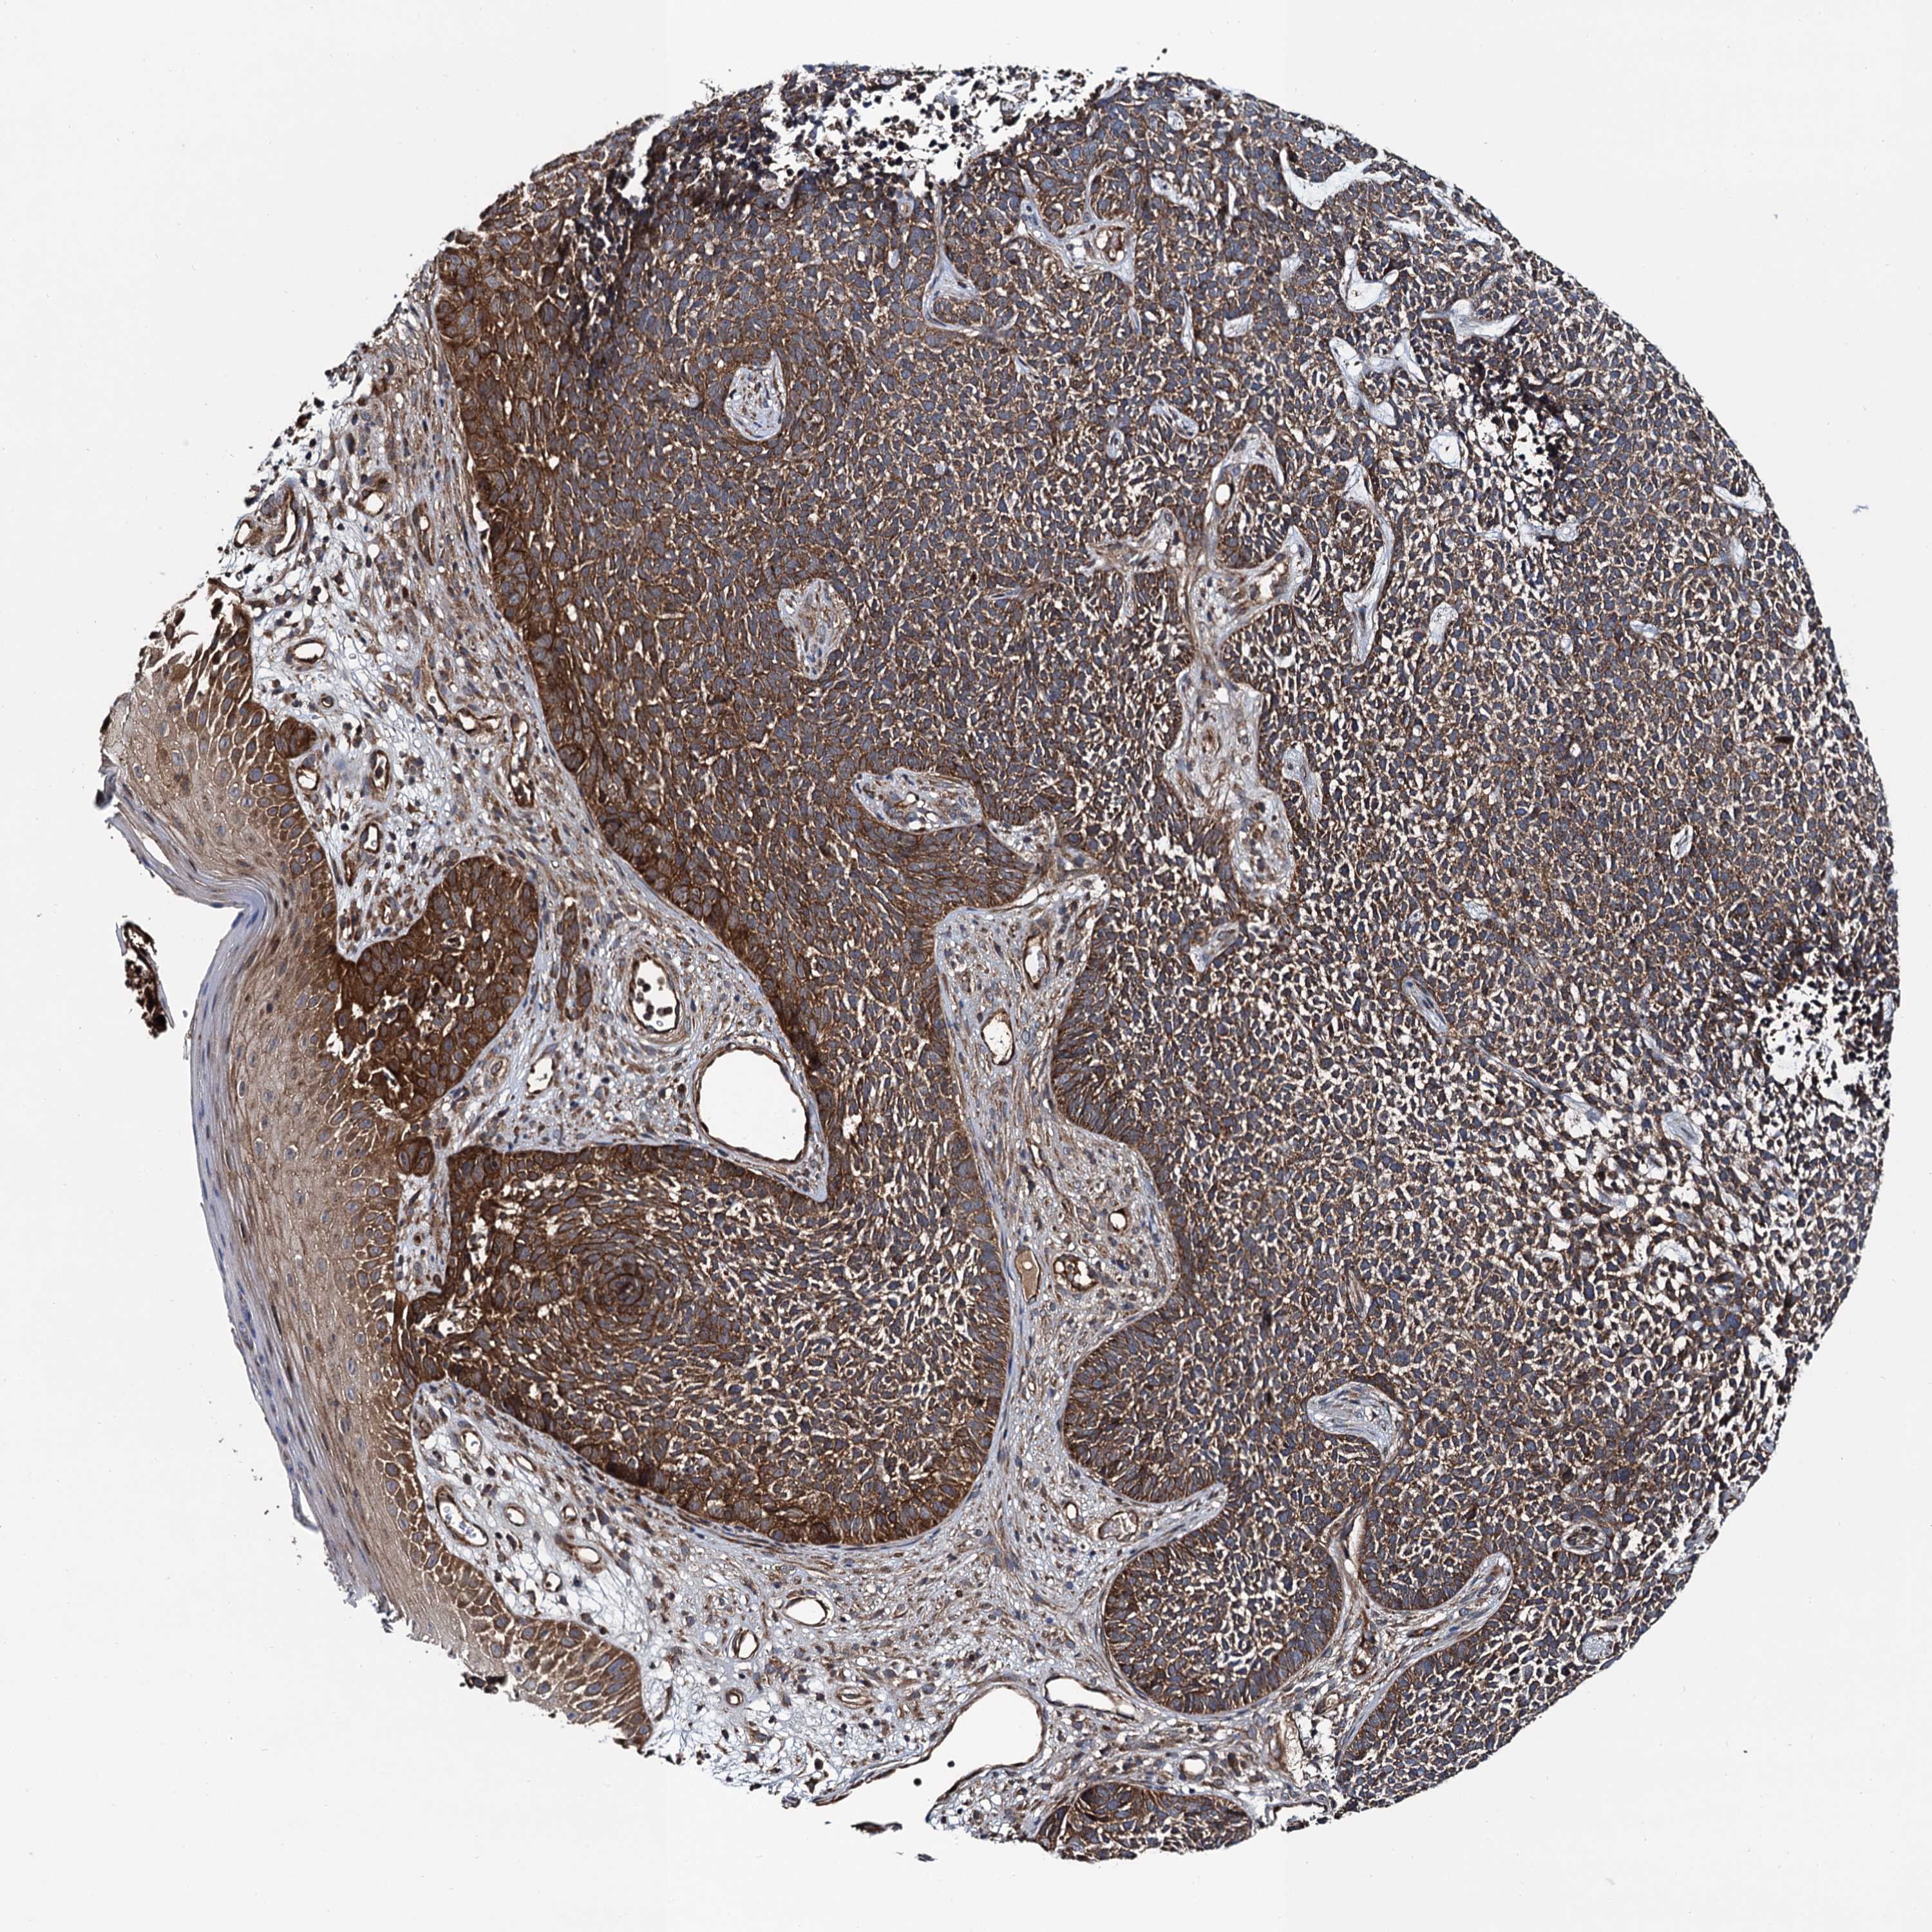

CANCER SKIN CANCER Show tissue menu

Basal cell and squamous cell cancer

SKIN CANCER - Protein expressioni

A mouse-over function shows sample information and annotation data. Click on an image to view it in a full screen mode. Samples can be filtered based on level of antibody staining by selecting one or several of the following categories: high, medium, low and not detected. The assay and annotation is described here.

Each image is clickable and will lead to virtual microscopy that enables deeper exploration of all samples and also displays staining intensity scores, fraction scores and subcellular localization as well as patient and tissue information for each sample.

Antibody HPA020873

Antibody HPA040413

Basal cell carcinoma

Squamous cell carcinoma, NOS

Squamous cell carcinoma, metastatic, NOS